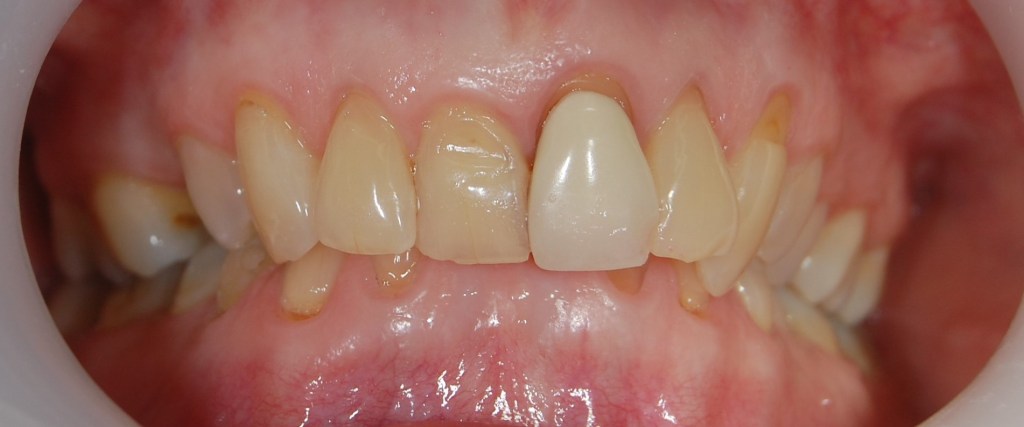

Kozmetikai kezelés: jobb felső kettes fog híddal történő pótlása, bal felső régi fémkerámia korona cseréje.

A választott korona típusa: CAD/CAM (komputer vezérelt tervezés/megmunkálás) technológiával készült cirkónium (fémmentes) szóló koronák.

A választott fogszín: A1 .

A protetikai munka elkészülésének ideje: 5 munkanap.